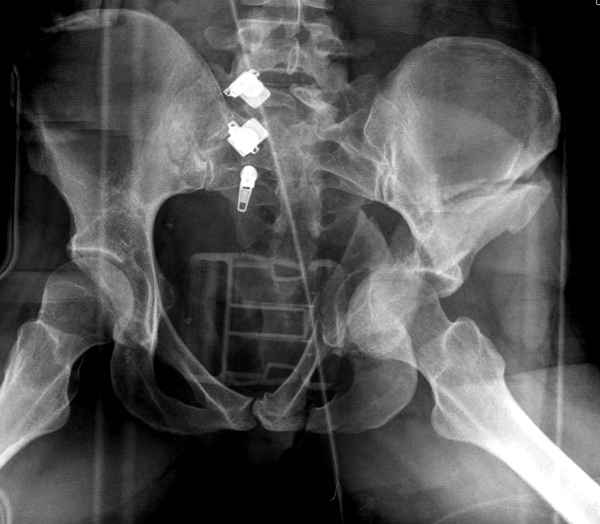

По-моему, надо готовить больного к будущей артропластике, но без опоры на задний столб невозможно удержать протез. Опорная конструкция (кольца и т.д.) должны иметь опору, и поэтому мы бы сделали реостеосинтез задним доступом. При надобности остеотомия и рутинная фиксация с межколонными винтами.

Здесь несколько вариантов двухколонных свежих переломов, которые были оперированы из одного-заднего, а также из двух: переднего и заднего доступов.